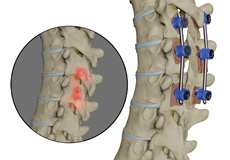

Lumbar Fusion

Spinal fusion, also called arthrodesis, is a surgical technique used to join two or more vertebrae (bones) within the spine. Lumbar fusion is the procedure of fusing the vertebrae in the lumbar portion of the spine (lower back). A piece of bone, taken from other parts of the body or donated from a bone bank is transplanted between the adjacent vertebrae. Screws, plates, or cages may be used with the bone graft to help hold the spine.

Spinal fusion, also called arthrodesis, is a surgical technique used to join two or more vertebrae (bones) within the spine. Sacroiliac Joint Radiofrequency Ablation is the procedure of fusing the vertebrae in the lumbar portion of the spine (lower back). A piece of bone, taken from other parts of the body or donated from a bone bank is transplanted between the adjacent vertebrae. Screws, plates, or cages may be used with the bone graft to help hold the spine.

Spinal fusion, also called arthrodesis, is a surgical technique used to join two or more vertebrae (bones) within the spine. Lumbar fusion is the fusion the vertebrae in the lumbar portion of the spine (lower back).

Lumbar interbody fusion (LIF) surgery is a surgical technique that involves the removal of a damaged intervertebral disc and the insertion of a bone graft into the disc space created between the two adjoining vertebrae. Bone grafts promote healing and facilitate fusion. Screws and rods are used to stabilize the spine during the healing process.

Spinal Fusion

Spinal fusion is the surgical technique of combining two or more vertebrae. A fusion of the vertebrae involves the insertion of secondary bone tissue obtained either from an autograft (tissues from your own body) or allograft (tissues from another person) to enhance the bone healing process.

Lumbar Spinal Fusion

The surgical technique of combining two or more vertebrae is known as spinal fusion. Back pain due to abnormal motion of the vertebrae is treated by this procedure.